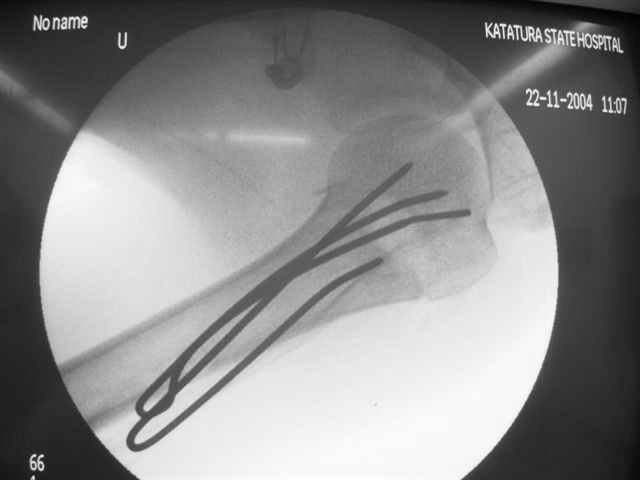

Женя, а как ты водишь спицы, в смысле, как делаешь входное отверстие, и как в него проводишь V-спицу? А то о дна из спиц, та, у которой не дошла до головки одна палочка буквы V, как-то выглядит на рентгенограмме, как будто или через очень большое отверстие введена, или каждая половинка через отдельные отверстия.

Мне кажется, проблема в том, что не все концы спиц зашли в головку, и зашедшие - недостаточно далеко прошли.

Спицы провожу по передней и задней поверхностям плечевой кости через 4,5 мм отверстия на разных уровнях.

Уточни - обе части буквы V вводишь в одно отверстие? А то по снимкам выглядит, что в разные.

V-спица проводится через 4,5 мм отверстие. Видимо, из-за разной длины вторая половина спицы *пролетела* мимо отверстия, что и привело к вторичному смещению костных фрагментов.